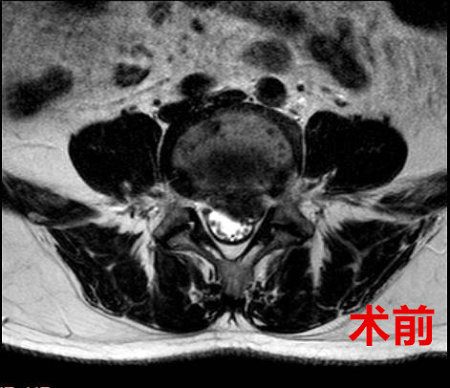

术前、术后腰椎核磁共振